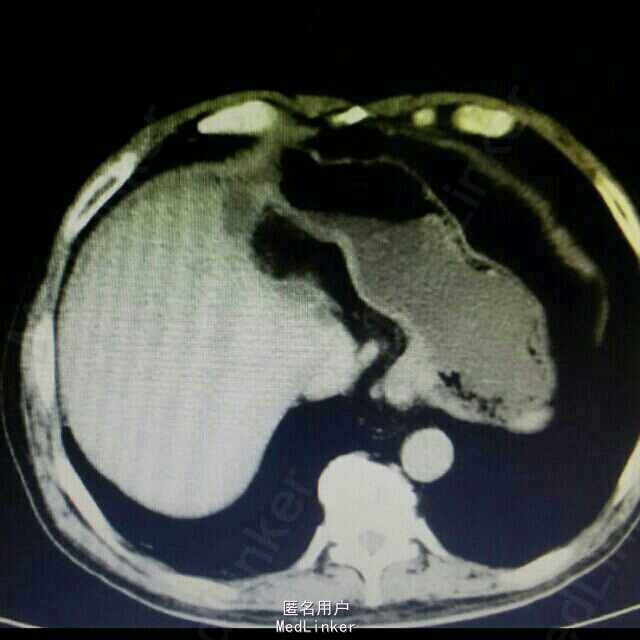

1、 主诉:上腹部疼痛4年余,加重2月。 2、 现病史:患者4年前无明显诱因出现上腹间歇性胀痛,可忍受,伴反酸、恶心、无呕吐,未予以治疗。患者2月前上腹部通天症状加重,伴肩部放射痛,伴反酸、恶心、无呕吐,未予以治疗。患者15天前因“感冒”就诊于当地医院行胸部CT示:肝左叶胆管结石并肝内胆管扩张、肝左叶萎缩。今患者为进一步治疗,前来我院就诊,门诊以“胆囊结石并急性胆囊炎”收入院,患者自发病以来精神状态可、食欲差,睡眠良好,大、小便正常,体重无明显变化。

3、 辅助检查:上腹部 CT平扫示:肝左叶胆管结石并肝内胆管扩张、肝左叶萎缩。胆囊结石,双肾囊肿。